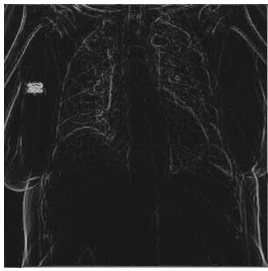

Second: the performance metrices for the proposed edge detection technique is measured for infected sample images using MATLAB and Zynq702 FPGA. The results of these performances are shown in Table 3.

Table 2 and Table 3 illustrate both the healthy and infected images, respectivly, the clarity of edges is observed. The tables indicate that using the proposed method with MATLAB led to a significant improvement in edge clarity in the Infected images compared to the healthy ones. This is due to the characteristics of the COVID-19 disease present in the infected images, which increase the complexity of the edges and make them less clear. They also indicate that the images produced by the proposed method are clearer than those from MATLAB, as the proposed method employs fixed-point arithmetic to represent numbers that are closer to edge values than the numbers used by MATLAB, which relies on floating-point arithmetic.

Table 3. Results for COVID-19 infected images

Input Image

MATLAB Result

FPGA Result